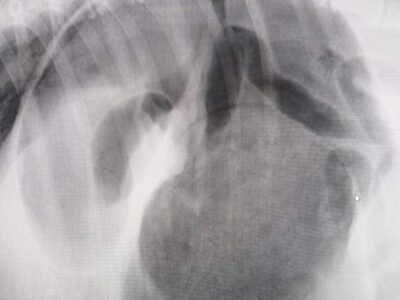

gastric foreign body in lateral

gastric foreign body in lateral -

gastric foreign body in DV

gastric foreign body in DV -